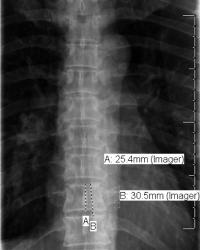

Figure - 13

"Vertebral body is internal ruler." Dorsal spine X-ray average 2.5cm height lower dorsal area. 3cm = distance between adjacent superior (or inferior) plates. |